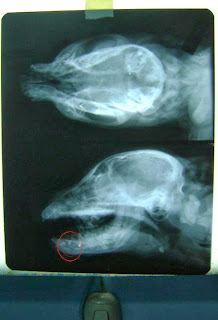

Las fotos que acontinuacion se muestran son de alto impacto se recomienda discrecion:

SE REALIZO UNA CIRUGÍA RECONSTRUCTIVA PARA UNIR EL TEJIDO DE LA CARITA, AUN SE ESTA VIENDO SI ES NECESARIO INSERTARLE UN CLAVO EN LA MANDÍBULA DEBIDO A QUE SE ENCUENTRA FRACTURADA,POR SU CORTA EDAD ES POSIBLE QUE PUEDA SOLDAR SOLA, HASTA MAÑANA SABREMOS.